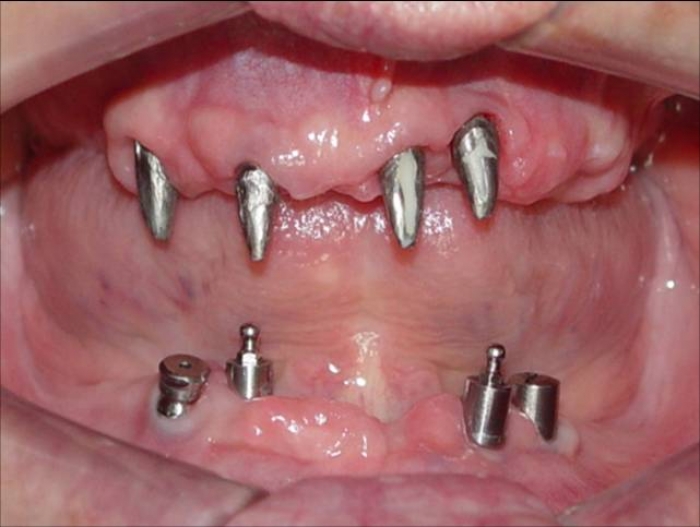

Imagens iniciais, dos dentes e implante comprometidos realizados por outro profissional